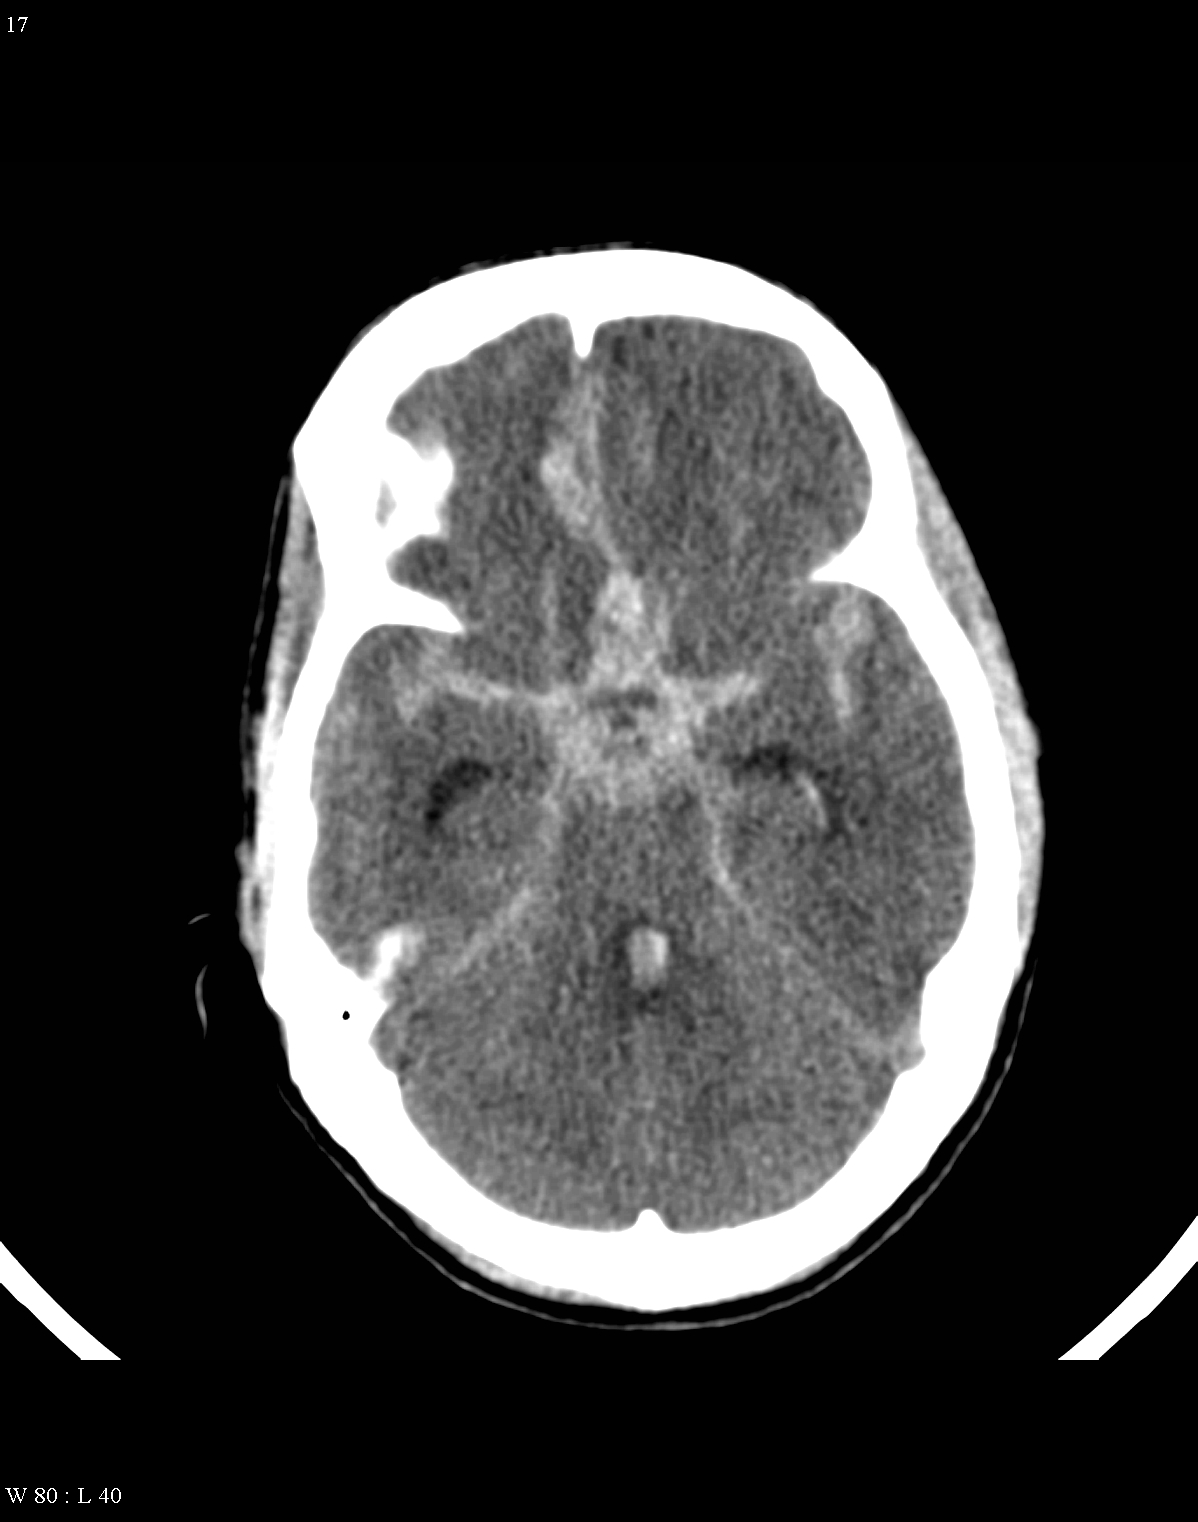

On CT images acute bleeding always presents as hyperdensity. (One has to keep it mind that hyperdensity of the blood is affected by the hematocrit levels, hence making the diagnosis more difficult.) Intraparenchymal blood is dominated by a destructive appearance (mass-effect) and it is surrounded by hypodensity as a sign of perifocal edema. It often breaks into the ventricles. In patients lying in a supine position they collect (sediment) at the occipital horn of the lateral ventricles, creating a hyperdense liquid-to-liquid levels. Later on, the density of blood decreases and shows a peripheral ring or rim-like contrast enhancement without mass-effect.

Although, subarachnoid hemorrhage (SAH) is most often caused by the rupture of a berry aneurysm, arteriovenous malformation (AVM) and trauma can also lead to it. SAH is typically located at the basal subarachnoid spaces, which then propagates along the lateral fissures or it fills up the interhemispheric fissure till the convexities. The main collection of the blood is usually indicative of the source of origin. In cases of parenchymal spread the mechanism, whether it broke in, or it broke out from the parenchyma could represent a differential diagnostic challenge. When accompanied by brain edema, the consequent herniation can result in parenchymal infarcts as well.

CT angiography examination is usually advisory in order to confirm the site of the bleeding. It is also effective when a hemorrhagic tumor is in the differentials, although complete differentiation might only be achieved by follow-up examinations. CTA is also essential in the diagnostics of multiple aneurysms (which are prevalent in 20-30% of the cases based on autopsy reports.) In case of a subarachnoid hemorrhage the consequently developing hydrocephalus and its degree might only be detected on follow-up CT examinations. It is very important to note that an initial brain aneurysm rupture might be followed by a second one within the first 7 – 10 days and the resulting vasospasm carries a much higher risk of mortality than the one at the time of the first SAH. This is why the scrutonius review of the acute diagnostic imaging is essential and it plays a fundamental role in patient treatment. Open brain surgery of the aneurysm (clipping) has been replaced by catheter angiography (DSA) nowadays. The aneurysm is either filled up with thrombogenic coils through its neck or recently bypassing stents are inserted to exclude the aneurysm from the cerebral circulation.